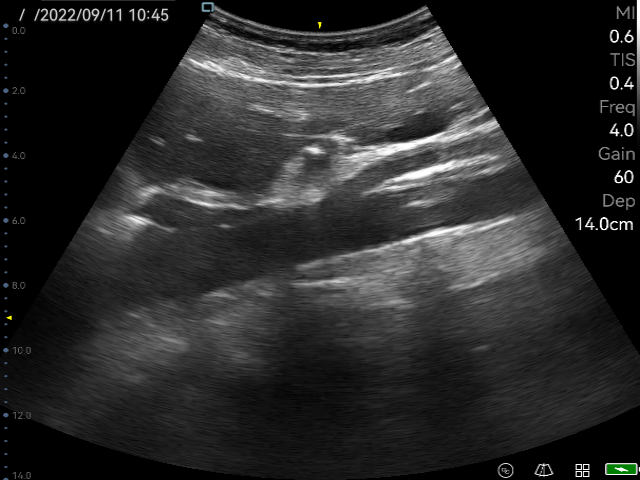

Image Quality and Resolution

The P50 adopts an advanced front-end image processing and post-processing platform. As a result, the P50 provides incredible detail resolution and contrast resolution, nearly equal to traditional-mid range ultrasound systems. With amazing image quality, doctors are able to make more accurate clinical decisions.